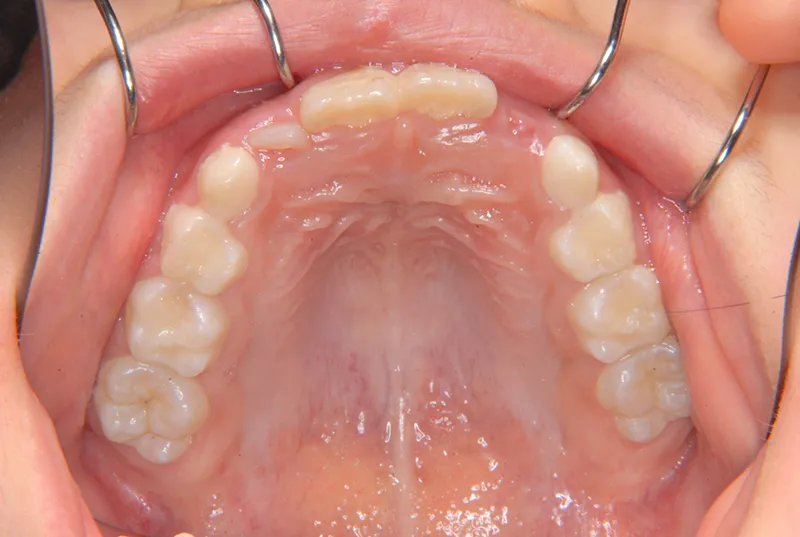

【子供の矯正(一期)】叢生・反対咬合・受け口・非抜歯症例・7歳女児【M.H様】

初診時年齢 小学校1年生 (女性) 主訴 受け口

診断名 叢生・反対咬合 装置名

状態 永久歯が生える隙間がない(叢生)

受け口(下顎前突/反対咬合)

下顎が大きい傾向があります。

上下の真ん中にズレがあるのと、上下とも永久歯の生えるスペースがせまいため、オリジナル矯正装置でスペースを作り、受け口も改善していきます。

治療回数21回、2年7ヶ月の治療期間で矯正治療を終了しました。

主訴が改善され、ご満足頂きました。